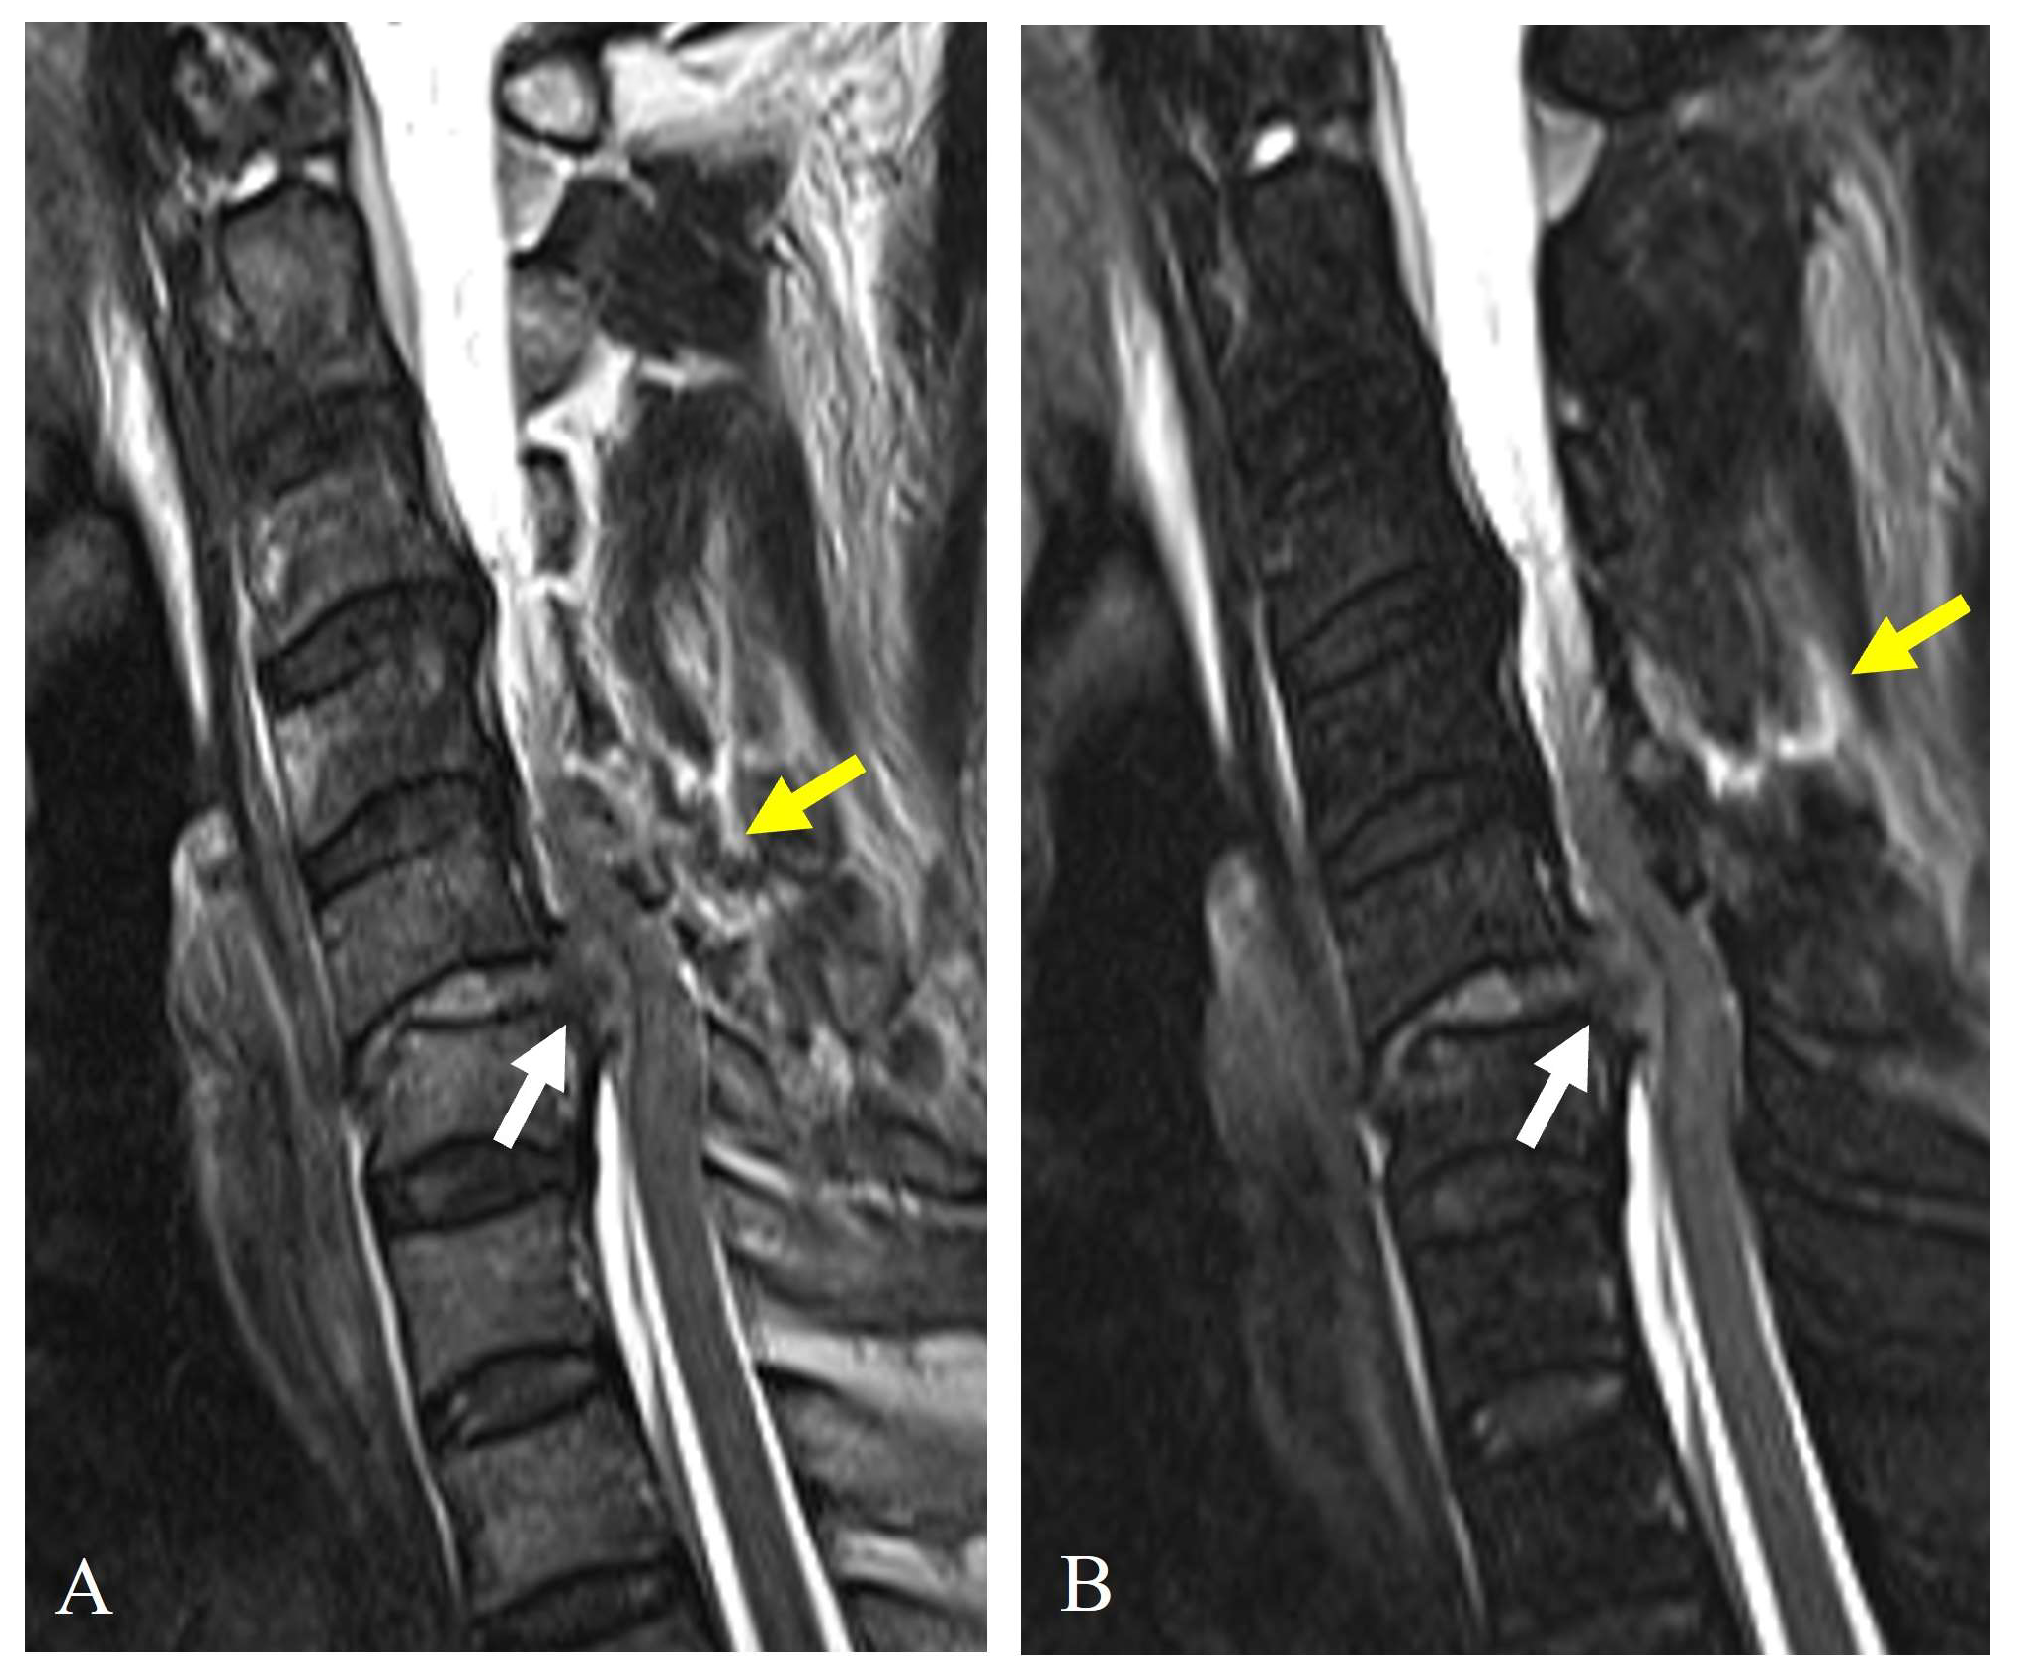

3.3. Magnetic Resonance Imaging (MRI)

7.2.1. Direct Compression or Stretching

- (1)

- Unilateral or bilateral facet dislocation can cause excessive rotational and translational forces on the vertebral artery, particularly at C3–C6 levels.

- (2)

- Perched or locked facets can lead to excessive stretch or kinking of the artery within the transverse foramen.

- (3)

- Fracture of the lateral mass or pedicle can lead to direct bony impingement on the vertebral artery (Figure 8).